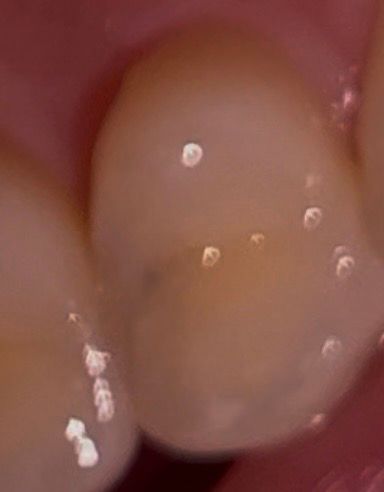

치과에서 육안으로 치아색이 다르다고

• 2번 째 사진

1. 사진 좌우 반전되거나 수정한게 아니라면 임상사진은 15,14번이고, 방사선 사진은 24,25 입니다

2. 14,15는 명백히 충치 있어보입니다